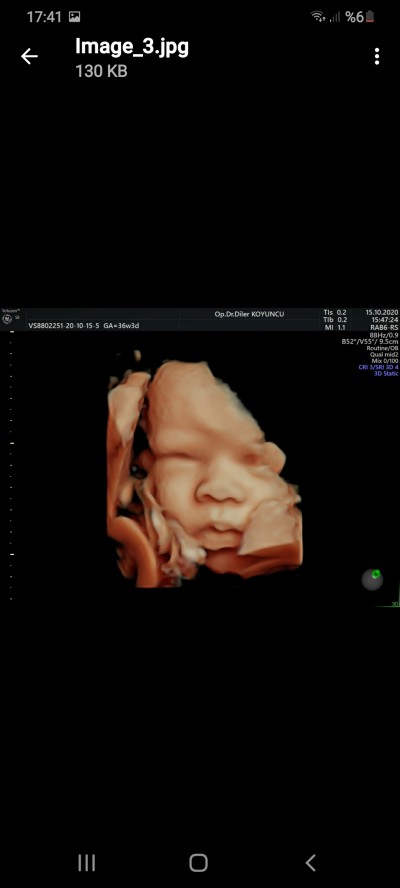

(517 puan)

image

dün kontrolüm vardı doktora gittim bebek dogum pozisyonunu almıs 29hafta 5 günlük fotoğrafını verdi vermesi gerekıyor görünmeyecek olsa bnimki görünmezdi sadece yüzünü gördüm vucudunu göstermedi

(878 puan)

Maşallah minik kuzuya